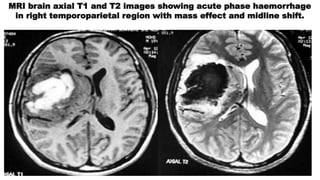

Magnetic resonance imaging

 T1 – most of the patent aneurysms appear as flow void or they

may show heterogeneous signal intensity

In thrombosed aneurysms the appearance depends on the age of

clot within the lumen

T2 – typically hypodensed

- laminated thrombus may show a hyper intensed rim

MRI brain axial T1 and T2 images showing acute phase haemorrhage

in right temporoparietal region with mass effect and midline shift.

Magnetic resonance imaging T1 – most of the patent aneurysms appear as flow void or they may show heterogeneous signal intensity In thrombosed aneurysms the appearance depends on the age of clot within the lumen T2 – typically hypodensed - laminated thrombus may show a hyper intensed rim

MRI brain axialT1 and T2 images showing acute phase haemorrhage in right temporoparietal region with mass effect and midline shift.